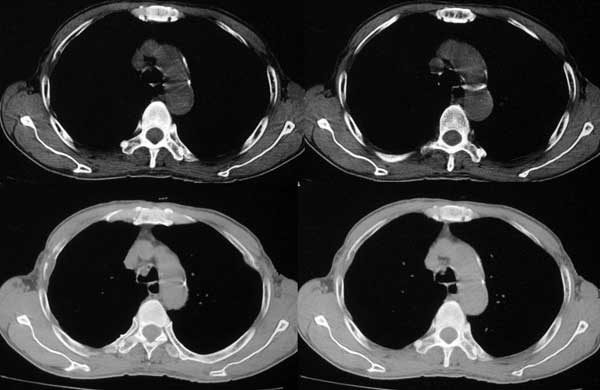

患者,男79岁,左侧肾癌术后5个月。近三个月,咳嗽时有痰中带血。

本例病人肺内多发结节灶、双侧肋骨破坏、胸椎椎体及椎弓破坏应是肾癌转移。请大家分析气管内结节灶性质?另外还得麻烦领导给删掉那多余的那幅图。谢谢了!

双肺多发结节状影,腹膜后见肿大淋巴结,支持肾ca转移

气管内结节灶性质是粘痰核?因为纵隔窗看不见

手术是怎么做的,好像没做。右肾还有两个病灶。气管腔内的那个结节密度确实很低,考虑粘痰核应该没问题,若是新生物不会这么低。不过挂在前壁上了,少见!

肺及胸膜下多发结节影,胸椎及附件、肋骨破坏支持转移癌。气管内结节影支持痰核。肾脏ct应该是术前的吧?左肾内亦见一低密度灶,另外胰腺好像也不规则。不知术后结果如何?

双肺内多发结节影是转移灶没问题,气管内的还应该商榷

肺内 肋骨 椎体转移已确定,气管内阴影不象结节,气管内壁无增生,显示层面只有一层,纵隔窗见不到,多考虑粘痰核.